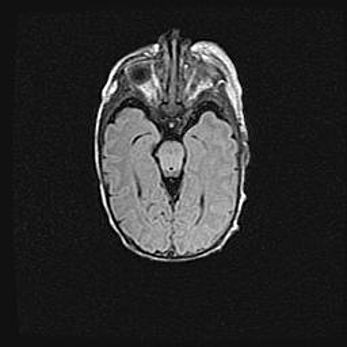

Лейкомаляция с кистозно-глиозной дегенерацией головного мозга.

Возраст: 2 месяца 25 дней

Вес: 6400 г

Окружность головы: 40 см

Срок гестации: 41 неделя

Лейкомаляцию относят к ишемически-гипоксическим повреждениям головного мозга, диагностируемым у новорожденных. При лейкомаляции в головном мозге обнаруживают очаги некроза, возникшие после тяжелой гипоксии и нарушения кровотока. В процессе морфогенеза очаги проходят три стадии: 1) развития некроза, 2) резорбции и 3) формирования глиозного рубца или кисты. Перивентрикулярная лейкомаляция (ПЛ) встречается примерно в 12% случаев среди новорожденных, обычно – у недоношенных детей, причем, частота ее зависит от массы, с которой младенец появился на свет. Наибольшее число малышей страдает лейкомаляцией, если масса при рождении 1500-2500 г.